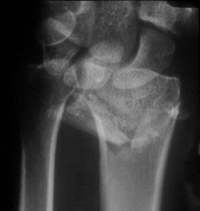

Durch den Zug am Bandapparat läßt sich die Fraktur exakt reponieren

Auch in der Aufsicht läßt sich die Fraktur stufenfrei reponieren.